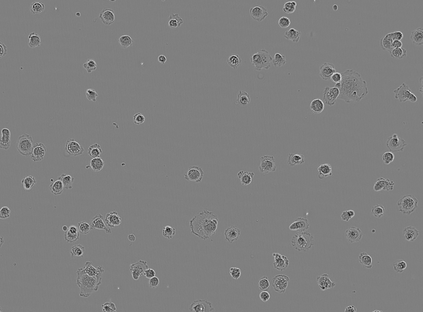

Bright-field microscopy, a cost-effective solution for live-cell culture, is often the only resource available, along with standard CPUs, for many low-budget labs. The inherent challenges of bright-field images -- their noisiness, low contrast, and dynamic morphology -- coupled with a lack of GPU resources and complex software interfaces, hinder the desired research output. This article presents a novel microscopy image analysis framework designed for low-budget labs equipped with a standard CPU desktop. The Python-based program enables cytometric analysis of live, unstained cells in culture through an advanced computer vision and machine learning pipeline. Crucially, the framework operates on label-free data, requiring no manually annotated training data or training phase. It is accessible via a user-friendly, cross-platform GUI that requires no programming skills, while also providing a scripting interface for programmatic control and integration by developers. The end-to-end workflow performs semantic and instance segmentation, feature extraction, analysis, evaluation, and automated report generation. Its modular architecture supports easy maintenance and flexible integration while supporting both single-image and batch processing. Validated on several unstained cell types from the public dataset of livecells, the framework demonstrates superior accuracy and reproducibility compared to contemporary tools like Cellpose and StarDist. Its competitive segmentation speed on a CPU-based platform highlights its significant potential for basic research and clinical applications -- particularly in cell transplantation for personalised medicine and muscle regeneration therapies. The access to the application is available for reproducibility